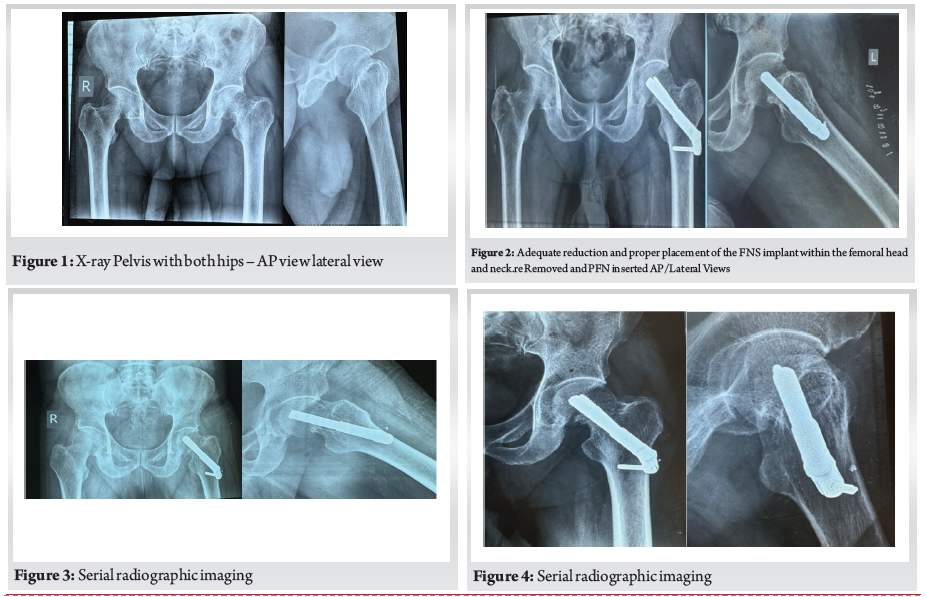

Postoperative Course and Complications (Fig. 2). Initial postoperative radiographs demonstrated adequate reduction and proper placement of the FNS implant within the femoral head and neck.

However, at five months post-surgery, despite the implant initially holding well, the patient experienced mild pain. Follow-up (Fig. 3) radiographs revealed concerning findings.

Loss of Reduction and Non-Union: The fracture line remained visible across serial films, with no evidence of trabecular bridging or cortical continuity, indicating an established non-union. Mild rounding of the proximal femoral fragment further supported this diagnosis. (Fig. 4)

Implant Cut-out: Progressive superior migration of the fixation screw was observed, breaching the subchondral bone of the femoral head. This indicated mechanical failure and loss of purchase, consistent with implant cut-out. (Fig. 5)

Femoral Head Changes: Early sclerotic changes were noted in the femoral head, raising suspicion for evolving avascular necrosis (AVN), likely exacerbated by delayed fixation and mechanical failure.